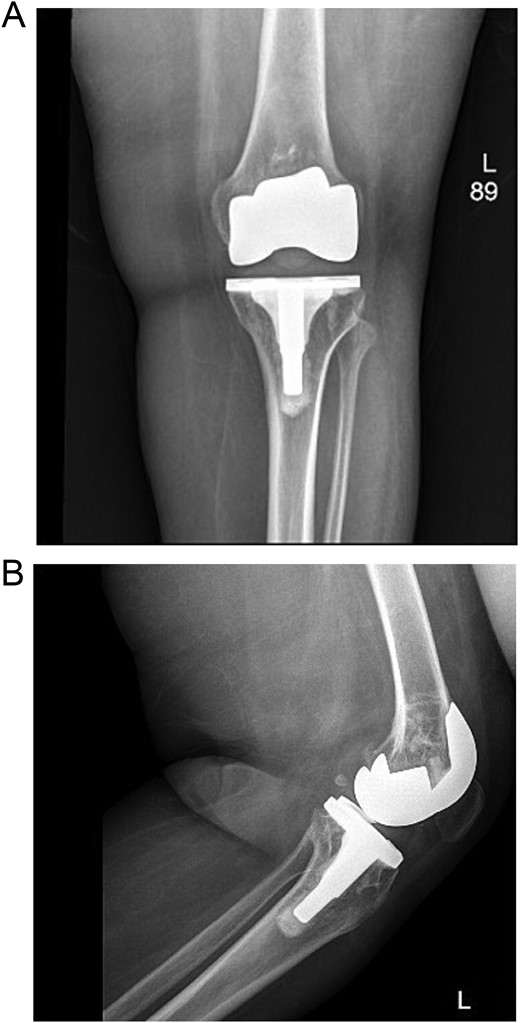

The patient was admitted for investigation. Routine radiographic imaging was unremarkable. Magnetic resonance imaging (MRI) and computed tomography scans were conducted and revealed no abnormalities (Figs 3 and 4). Afterward, the patient was examined under anesthesia, where a stable joint was noted with full knee ROM. The only remarkable finding was the clicking sound with flexion. The impression was that there was polyethylene wear due to the significant weight gain, and the decision was made to discharge the patient with instructions to lose weight and to re-admit electively for TKA revision and possible polyethylene exchange if there was no improvement.

Computed tomography (CT scan) of bilateral knees showing no abnormality.